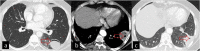

Hydatid cyst caused by the larval form of Echinococcus is a worldwide zoonosis. The lungs and liver are the most common sites involved. While the lung parenchyma is the most common site within the thorax, it may develop in any extrapulmonary region including the pleural cavity, fissures, mediastinum, heart, vascular structures, chest wall, and diaphragm. Imaging plays a pivotal role not only in the diagnosis of hydatid cyst, but also in the visualization of the extent of involvement and complications. The aim of this pictorial review was to comprehensively describe the imaging findings of thoracic hydatid cyst including pulmonary and very unusual extrapulmonary involvements. An outline is also given for the findings of complications and differential diagnosis of thoracic hydatid cyst.